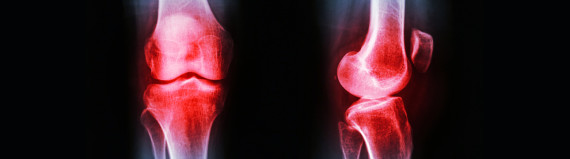

As your body ages, it naturally becomes harder to balance on your own two feet. Aging however, does not always account for the causes of balance disorder, which are relatively common issues that can often be treated with the help of physical therapy.